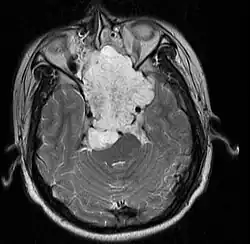

• Skull base:

• May be intracranial or extracranial, with mass effect symptoms depending on location

• Headaches and/or facial pain are common

• Pituitary insufficiency, hemianopsia/diplopia, cranial nerve deficits, nasal stuffiness.

Skull Base

• Hannover; 2007 (Germany) PMID 17695386 -- "Chordomas of the skull base: surgical management and outcome." (Samii A, J Neurosurg. 2007 Aug;107(2):319-24.)

• Retrospective. 49 patients. Transethmoidal approach 36%, pterional 23%, retrosigmoid 23%.

• Outcome: GTR 49%, subtotal resection 51%. Initial surgery GTR 78%. 5-year OS 65%, 10-year OS 39%